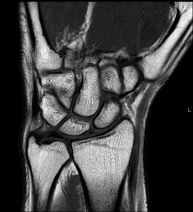

Exploración para el estudio de lesiones en tendones, músculos y nervios periféricos. Tiene una duración aproximada de 18 minutos. No emplea radiación ionizante. - RM Muñeca / carpo

Exploración para el estudio de lesiones en tendones músculos y articulación. Muy útil para la valoración de pequeñas fracturas inadvertidas, lesiones de ligamentos, y procesos inflamatorios y degenerativos (artritis y artrosis). Tiene una duración aproximada de 20 minutos. No emplea radiación ionizante. - RM Mano / dedos

Exploración para el estudio de las lesiones en pequeñas estructuras anatómicas de la articulación que suelen lesionarse en pacientes que sufren luxación o inestabilidad crónica. El estudio viene precedido por una inyección de contraste en el interior de la articulación, realizada bajo control de rayos X. La duración global de los dos procedimientos es de 50 minutos. - Artro-RM Muñeca

Exploración para el estudio de las lesiones en pequeñas estructuras anatómicas de sus articulaciones tales como ligamentos y cartílago. El estudio viene precedido por una inyección de contraste en el interior de una de las articulaciones, realizada bajo control de rayos X. La duración global de los dos procedimientos es de 50 minutos. - Artro-RM Cadera